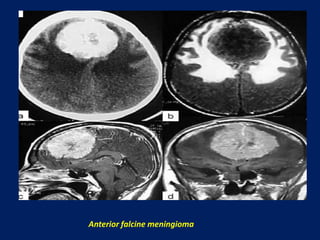

Anterior falcine meningioma